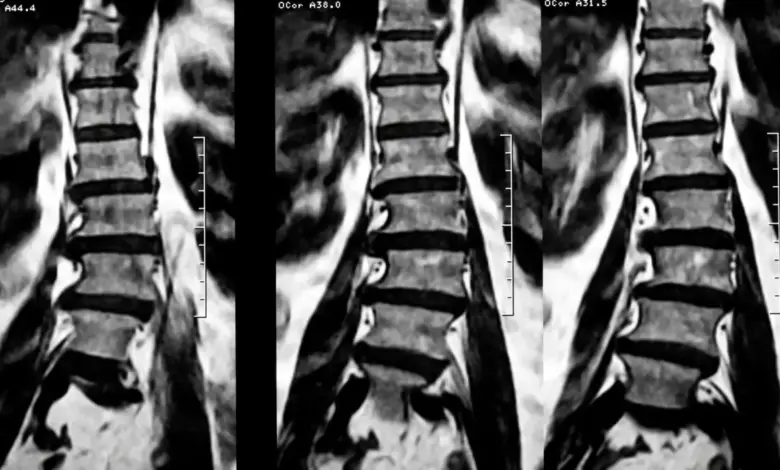

Radiografias são instrumentos essenciais para visualizar o grau de curvatura e identificar se há uma necessidade iminente de correção escoliose lombar.

Testes de flexibilidade também desempenham um papel importante para avaliar a funcionalidade espinhal e determinar a melhor forma de tratamento.

Por fim, o ângulo de Cobb é uma medida padrão utilizada para quantificar a severidade da escoliose, e dependendo do tamanho deste ângulo, o tratamento pode abranger desde práticas conservadoras até abordagens mais invasivas.